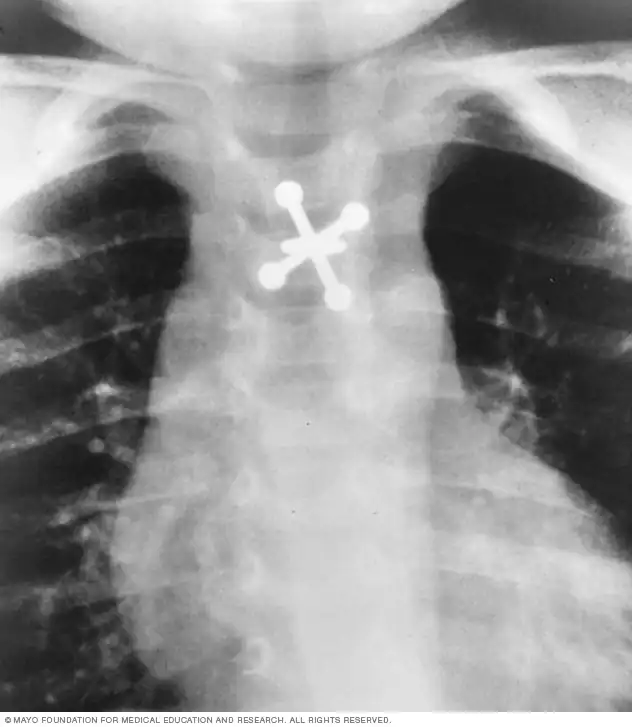

اشعه ایکس از جسم بلعیدهشده

اشعه ایکس میتواند اجسام فلزی بلعیدهشده توسط کودک را مشخص کند.

- اجسام بلعیدهشده: اگر کودک وسیلهای مثل کلید یا سکه بلعیده باشد، اشعه ایکس محل آن را نشان میدهد.